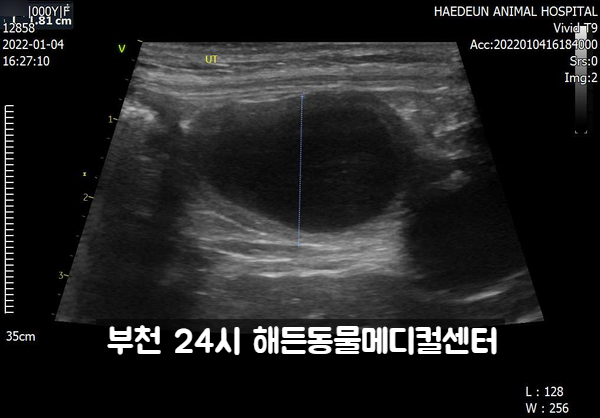

초음파 검사를 하겠습니다.

허든 초음파는 미국 GE사의 최신 vivid-T9 초음파를 사용합니다.영상전공의가 직접 검사라고 판독합니다.

초음파상에 자궁촉농증이 확인됩니다.

소장 종양이 의심됩니다.